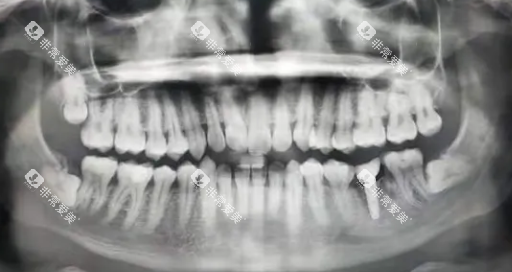

种植牙修复

种植牙是目前较为理想的牙齿缺失修复方式,其功能和美观度都接近天然牙。

在潍坊地区,种植牙的价格因种植体品牌、牙冠材料等因素而异。

一般来说,国产种植体的单颗价格在3000 - 8000元,进口种植体的价格在6000 - 15000元。

加上牙冠的费用,单颗种植牙的总费用大约在5000 - 20000元。